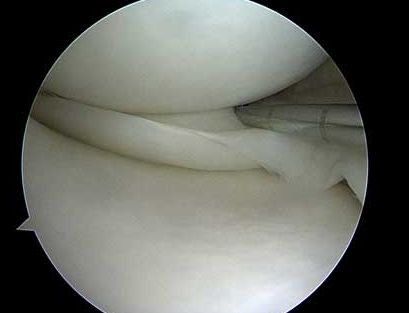

Meniskskador opereras med titthålskirurgi (artroskopi)

Menisken har inte har någon självläkande förmåga i den inre ⅔ av menisken. Sprickor i detta område måste oftast behandlas med att det skadade området tas bort.

Skador i den yttre ⅓ delen av menisken har läkningsförmåga om man stabiliserar-reparerar skadan, dvs. syr fast menisken.

Partiell meniskektomi

- Det vanligaste ingreppet, då de flesta skador är belägna i den inre ⅔ av menisken.

- Det trasiga flikiga området på menisken trimmas till en stabil, jämn kant.